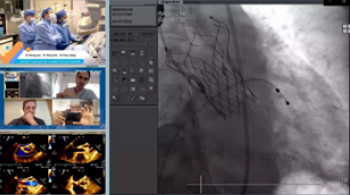

接受心血管介入培训

参加线上国际学术研讨(含手术直播)